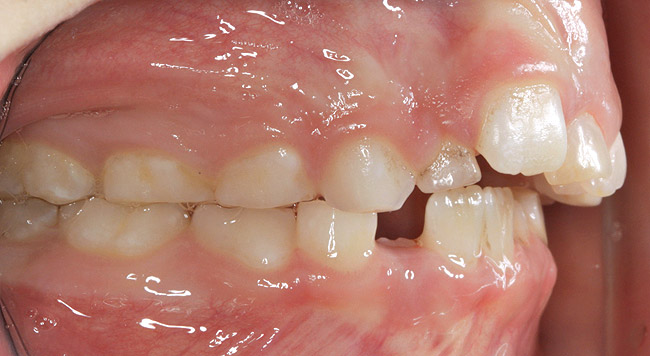

(4.) Patient presents bilateral crossbite and significant attrition. Father assists in retraction.

Figure 4